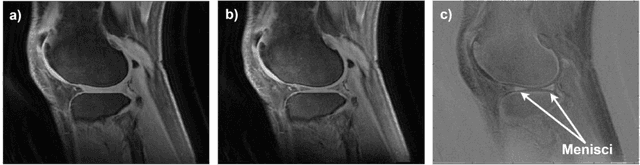

Abstract:The purpose of this work is to develop a deep learning-based method for knee menisci segmentation in 3D ultrashort echo time (UTE) cones magnetic resonance (MR) imaging, and to automatically determine MR relaxation times, namely the T1, T1$\rho$, and T2* parameters, which can be used to assess knee osteoarthritis (OA). Whole knee joint imaging was performed using 3D UTE cones sequences to collect data from 61 human subjects. Regions of interest (ROIs) were outlined by two experienced radiologists based on subtracted T1$\rho$-weighted MR images. Transfer learning was applied to develop 2D attention U-Net convolutional neural networks for the menisci segmentation based on each radiologist's ROIs separately. Dice scores were calculated to assess segmentation performance. Next, the T1, T1$\rho$, T2* relaxations, and ROI areas were determined for the manual and automatic segmentations, then compared.The models developed using ROIs provided by two radiologists achieved high Dice scores of 0.860 and 0.833, while the radiologists' manual segmentations achieved a Dice score of 0.820. Linear correlation coefficients for the T1, T1$\rho$, and T2* relaxations calculated using the automatic and manual segmentations ranged between 0.90 and 0.97, and there were no associated differences between the estimated average meniscal relaxation parameters. The deep learning models achieved segmentation performance equivalent to the inter-observer variability of two radiologists. The proposed deep learning-based approach can be used to efficiently generate automatic segmentations and determine meniscal relaxations times. The method has the potential to help radiologists with the assessment of meniscal diseases, such as OA.